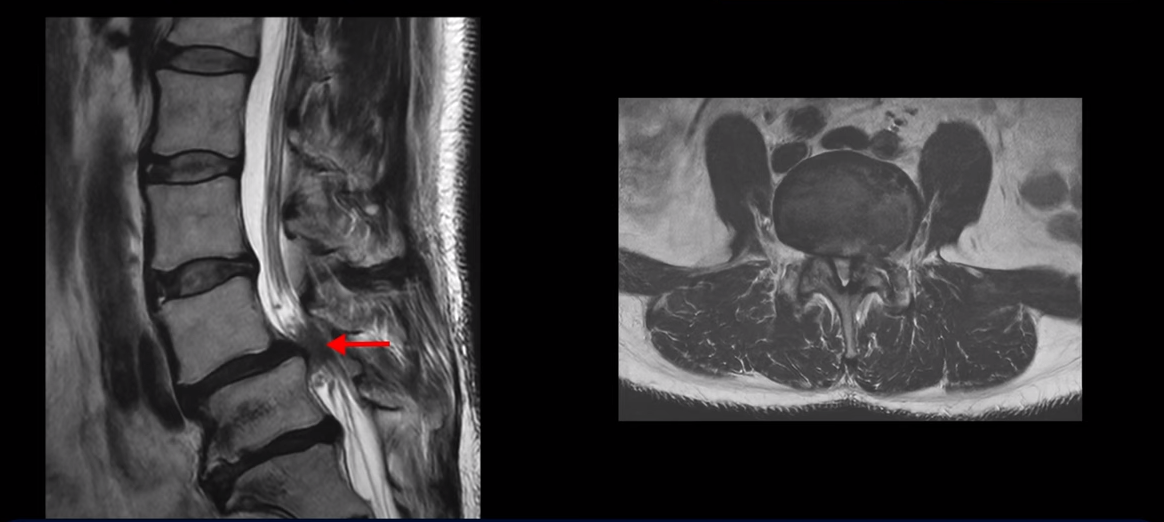

제가 먼저 이 환자분 MRI를 보면서 설명 드린 후 이분 말씀 더 들어보겠습니다. 보시다시피 두 마디가 심하게 퇴행되어 있고

4번 5번에는 척추뼈가 밀려나간 전방전위증이 있습니다.

4번 5번에 심한 중심성 협착도 있습니다.

전방전위증이 있는 분들은 뼈가 밀려 나가 있으므로 다른 사람들에 비해 협착이 더 빨리 더 쉽게 올 수 있습니다. 이분도 나이가 48세라는 젊은 나이인걸 고려하면 협착이 다른 분들에 비해 매우 빠르게 왔다고 볼 수 있습니다.

양쪽 신경 가지가 빠져 나가는 추간공도 왼쪽 오른쪽 모두 좁아져 있습니다.

5번 1번에는 가운데로는 디스크가 밀려나와 있습니다.

이건 아주 오래된 퇴행성디스크로 보입니다. 그래서 이 환자분은 양쪽 엉덩이와 다리가 모두 저리고 아픈 게 양쪽 추간공 문제 때문일 수도 있고 중심성 협착 때문일 수도 있습니다. 퇴행성디스크 때문에 아플 가능성은 상대적으로 적어보입니다.